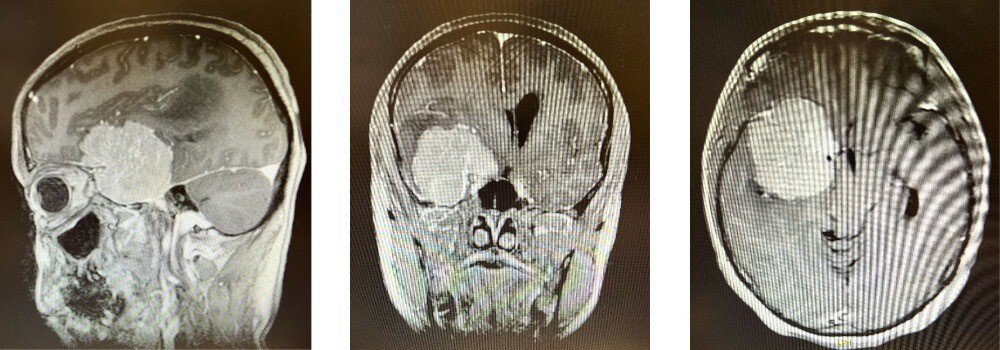

Later that day at the hospital, doctors immediately recognized what they saw on the scans in front of them: a giant meningioma on the left side of her brain. Though benign, it was particularly worrisome because of its size. Vandergrift, the surgeon who led the team during the four-hour procedure to remove the tumor, described it as “the size of a nice big orange at Trader Joe’s.”

A CT scan of Palmer's head before the operation shows the giant meningioma located in the left side of her brain.

Vandergrift explained that meningiomas – tumors that arise from the meninges, or membranes, which surround the brain and spinal cord – often grow slowly and typically come to attention due to circumstances unrelated to the tumor, like a fall from a ladder, a sinus infection or, in Palmer’s case, a suspected DUI. Their causes are varied, but one of the more common is exposure to radiation. Though Vandergrift and Palmer can’t know for sure, they both suspect her tumor might have gotten started 37 years ago, on that fateful April morning in 1986.